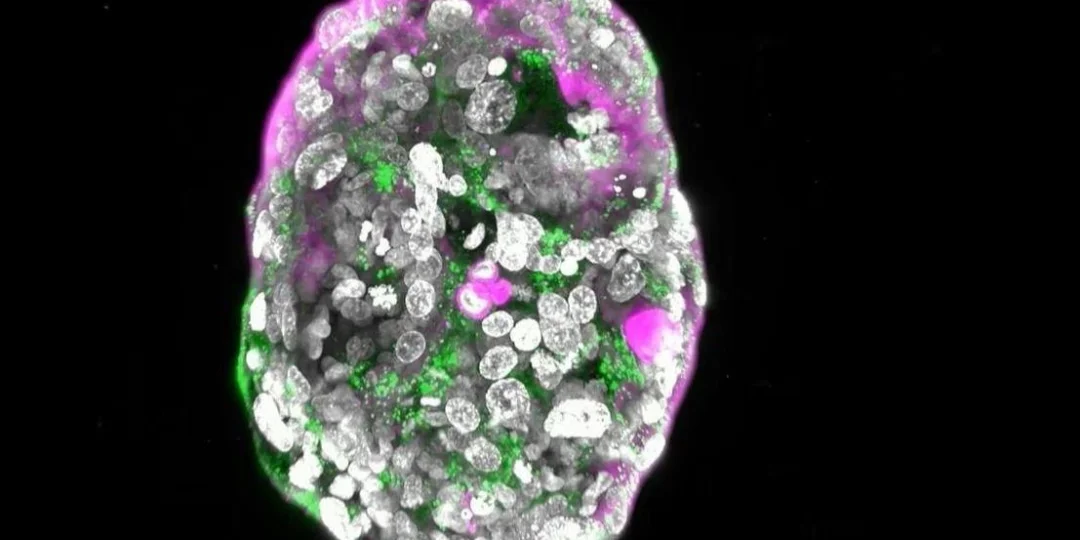

La ciencia acaba de generar un avance muy importante. El Instituto Weizmann de Ciencias de Israel logró desarrollar una entidad muy similar a un embrión humano temprano, pero sin utilizar espermatozoides, óvulos ni útero.

Los científicos informaron que crearon modelos completos de embriones humanos. Estos se cultivaron en laboratorio a partir de cédulas madres y los especialistas lograron que crecieran fuera de un útero hasta los catorce días de gestación.

El mismo equipo había conseguido crear modelos sintéticos de embriones de ratón, por lo que tenían experiencia en este tipo de investigaciones. “Dada su auténtica complejidad, los modelos de embrión humano obtenidos pueden brindar una oportunidad sin precedentes para arrojar nueva luz sobre los misteriosos inicios del embrión”, expresa el comunicado.